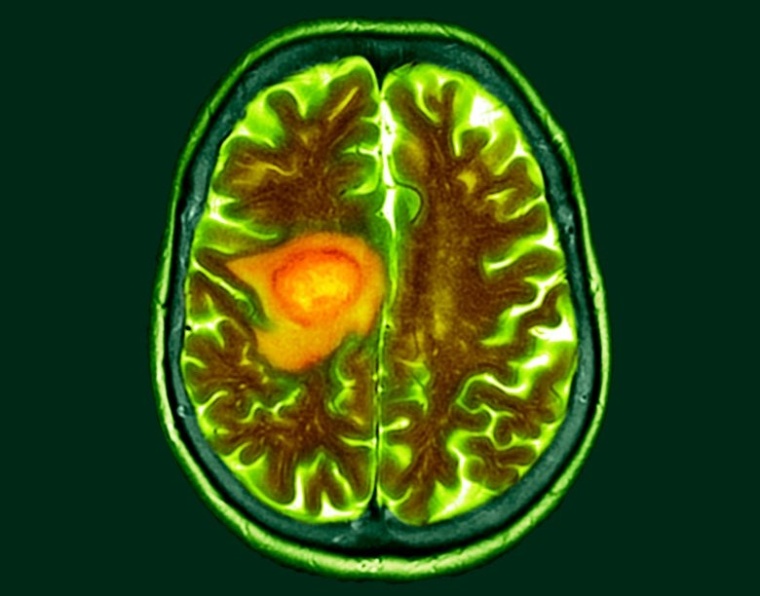

Neuer Ansatz für eine T-Zell-Immuntherapie gegen bösartige Hirntumoren

Forscher am Deutschen Krebsforschungszentrum (DKFZ) und an der Universitätsmedizin Mannheim (UMM) haben eine vielversprechende zelluläre Immuntherapie zur Behandlung von Glioblastomen entwickelt.